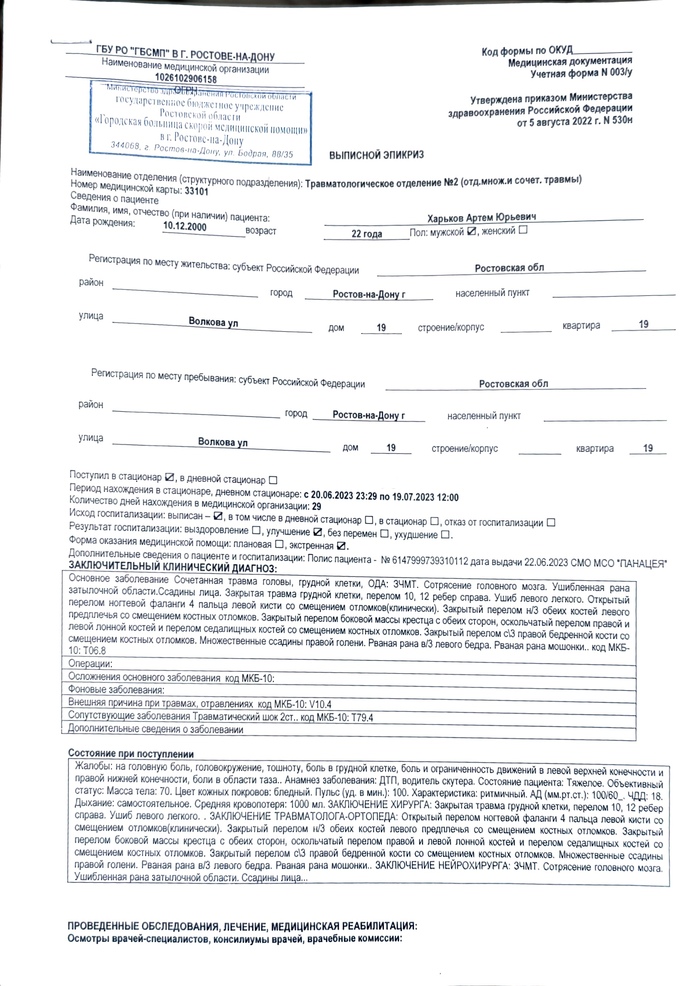

Я двигаясь по улице Сальский переулок в сторону улицы Вятской на зеленый сигнал светофора, влетев в автомобиль перелетел его, пробив головой стекло. Благодаря очевидцам которые во время оказали помощь и вызвали скорую, я остался жив, в то время как предполагаемая виновник аварии вышла из машины, ушла и начала кому то звонить. В последствии я провел в реанимации 7 дней, получил 7 переломов тела как закрытых так и открытых, разрыв тканей и сотрясение головного мозга и перенес множество операций и еще предстоит одна операция в августе этого года.

На данный момент мы добились возбуждения уголовного дела по 264 статье УК РФ «Причинение тяжкого вреда здоровью по неосторожности» Часть 1, данным исходом мы не удовлетворены так как согласно ст. 115 УК РФ данное преступление относится к категории преступлений небольшой тяжести, срок давности которой – 2 года со дня совершения преступления, зная как они затягивают дело, я боюсь что его могут просто закрыть в связи с истекшим сроком давности.